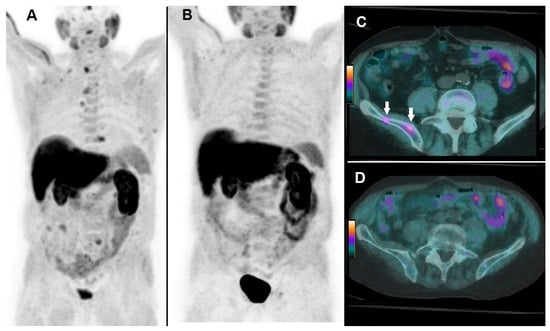

By Kaplan–Meier analysis, responders presented a significantly longer survival than non-responders (i.e., median OS = 19 months, 95% CI 15–27, vs. 8 months, 95% CI 7–13, p < 0.05), as shown by Figure 3. Emblematic examples of 18F-choline PET/CT findings in a patient with more favorable prognostic factors and clinical outcome are depicted in Figure 4, while Figure 5 describes a subject with poor prognostic factors and outcome.

Figure 5. A 66-year-old patient affected by mCRPC, previously treated with abiraterone acetate and docetaxel, then submitted to 223Ra-therapy. 18F-choline PET/CT acquired at baseline demonstrated multiple tracer uptake sites in bones, as evident in Whole Body (A); baseline pre-treatment parameters were as follows: PSA = 157 ng/mL; the number of lesions > 20; TLA = 3969.9 g. After 3 cycles, 223Ra-therapy was discontinued due to deterioration of patient’s performance status and increased PSA (i.e., 289 ng/mL). 18F-choline PET/CT acquired after 3 cycles of 223Ra-therapy demonstrated an impressive progression of skeletal disease, as shown by Whole Body (B). 18F-choline PET/CT fused images of the liver acquired at baseline did not show abnormal tracer uptake (C), while post-treatment axial slices demonstrated the appearance of a partially necrotic metastasis in the VIII/VII hepatic segment (D, white arrow). The patient’s OS resulted in 7 months.